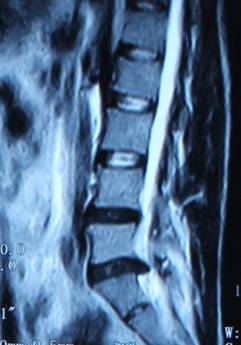

1.患者邹某,男,79岁,因“腰痛双下肢疼痛1年余,加重并间歇性跛行2月”于2014年3月26日入院。入院见患者腰痛病双下肢疼痛、麻木,间歇性跛行,行走约10余米,休息后略缓解。查:直腿抬高试验左40°(+),右55°(+),加强试验(+),腰背伸试验阳性。双侧膝腱未引出,跟腱反射减弱,双侧踇背伸肌力Ⅳ级。入院后诊断为腰椎管狭窄症。患者既往患糖尿病、高血压、冠心病病史。入院后完善检查,明确诊断,请相关科室会诊后认为手术风险极大。经科室讨论后行经皮椎间孔镜下髓核摘除并椎管扩大成形术,手术麻醉方式为局麻。于2014年3月29日行手术治疗,经椎间孔入路椎间孔镜下髓核摘除椎管扩大成形术。手术顺利,术中无出血,手术时间约40min。术中可与患者交流。术后患者即可感双下肢无疼痛,第二天佩戴腰围下地活动后双下肢无不适。术后半年复查腰椎MRI示突出髓核已摘除,神经根无受压。术后随访1年,患者目前病情恢复良好,无下肢疼痛、麻木,无间歇性跛行。

术前腰椎MRI